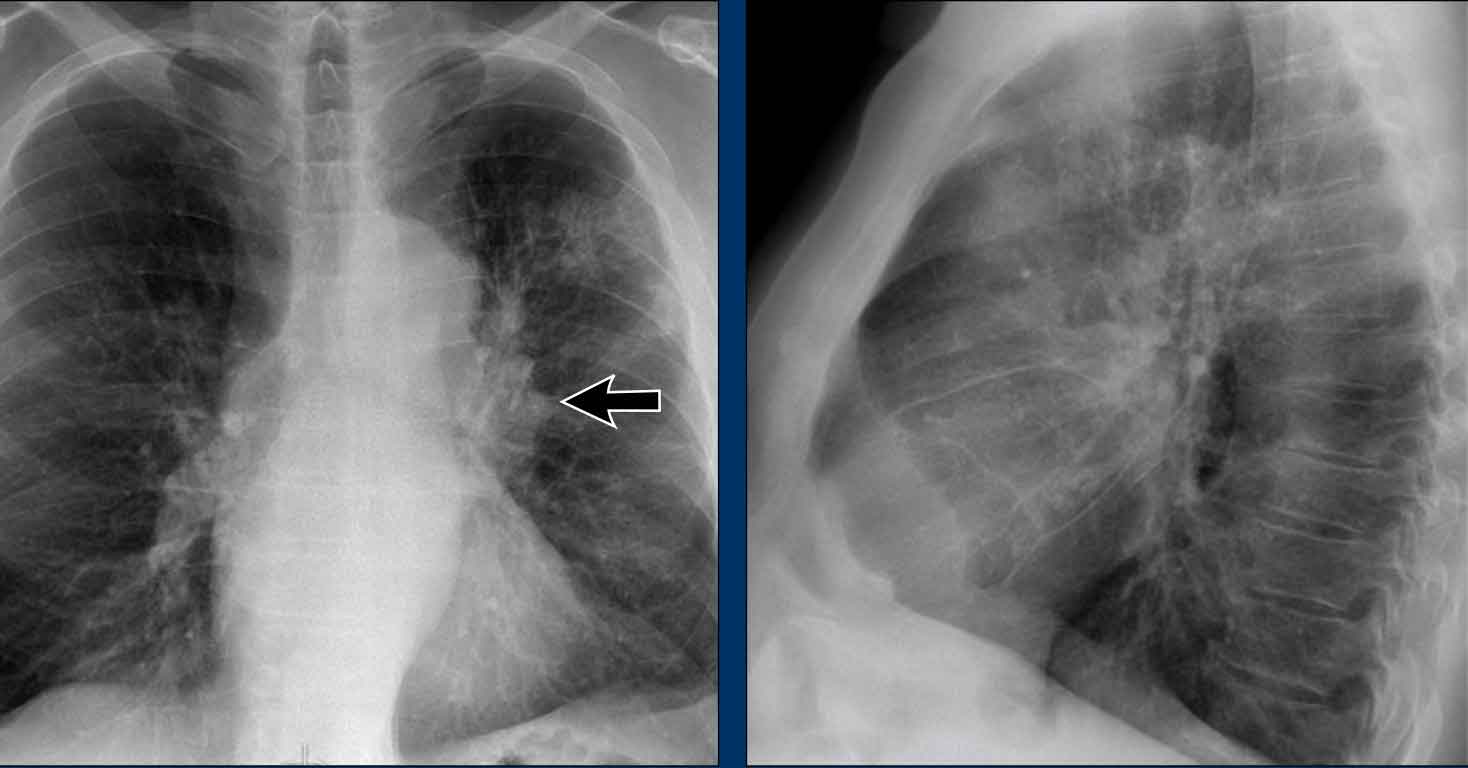

Hidden area (5): Mass Behind the First Rib

In some patients, an accessory joint at the anterior aspect of the first rib may simulate a mass, as we learned earlier.

However this area is also a "hidden zone", where true lesions can be masked.

- In this case, a small lung carcinoma was obscured by the left first rib on the PA view.

- On the lateral film, the lesion is visible in the retrosternal space.

Continue with the PET-CT...

Subsequent PET-CT imaging confirmed a hypermetabolic tumor (arrow), with metastases to the bone and liver.

- Diagnosis was confirmed via biopsy of an osteolytic metastasis in the iliac bone.